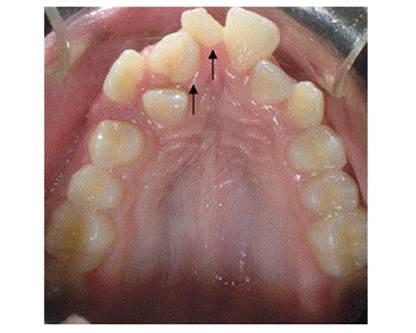

Figure 1 and Figure 2 show the front and occlusal images of an 11-year-old male patient who consulted the Universidad del Valle Clínica de Odontología Integral del Niño y del Adolescente. The patient does not have a history of relevant medical conditions or systemic conditions, nor background of dental anomalies of number in his family.

Figure 2 Occlusal view. The arrows point to the supernumerary teeth; note that these are two supplemental dysmorphic teeth

The patient had two mesiodens that have signifi cantly displaced the central incisors and lateral incisors. The mesiodens have the shape of incisors with multiple tubercles.

It is not common to find erupted upper permanent incisors in relation to molariform, supplemental, or tuberculate mesiodens, contrary to what happens with conical-shaped mesiodens.10)(32)(34) As opposed to what was reported in the literature in case 1 reported here, the presence of two mesiodens did not block eruption of the lateral right central incisor, although it resulted in displacement of the upper right central incisor to the zone corresponding to the right upper canine, as well as marked palatalization of the upper right lateral incisor, affecting the patient′s occlusal harmony, appearance, and functionality.